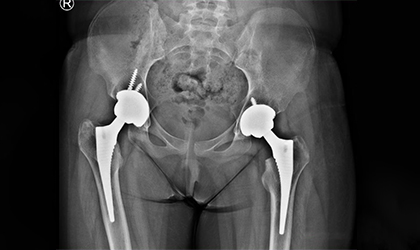

This is one of the youngest girls I have done a hip replacement in. Her right hip was replaced at the age of 13, followed by the left hip a year later. She is a blood cancer survivor who developed collapse of both hips due to the effects of chemotherapy — the same treatment that ultimately saved her life.She had ceramic bearings. Presently totally symptom free pursuing her higher studies.

Both hips had collapsed due to avascular necrosis secondary to chemotherapy. A tailored surgical plan was made to address the damage while considering her young age and medical history.